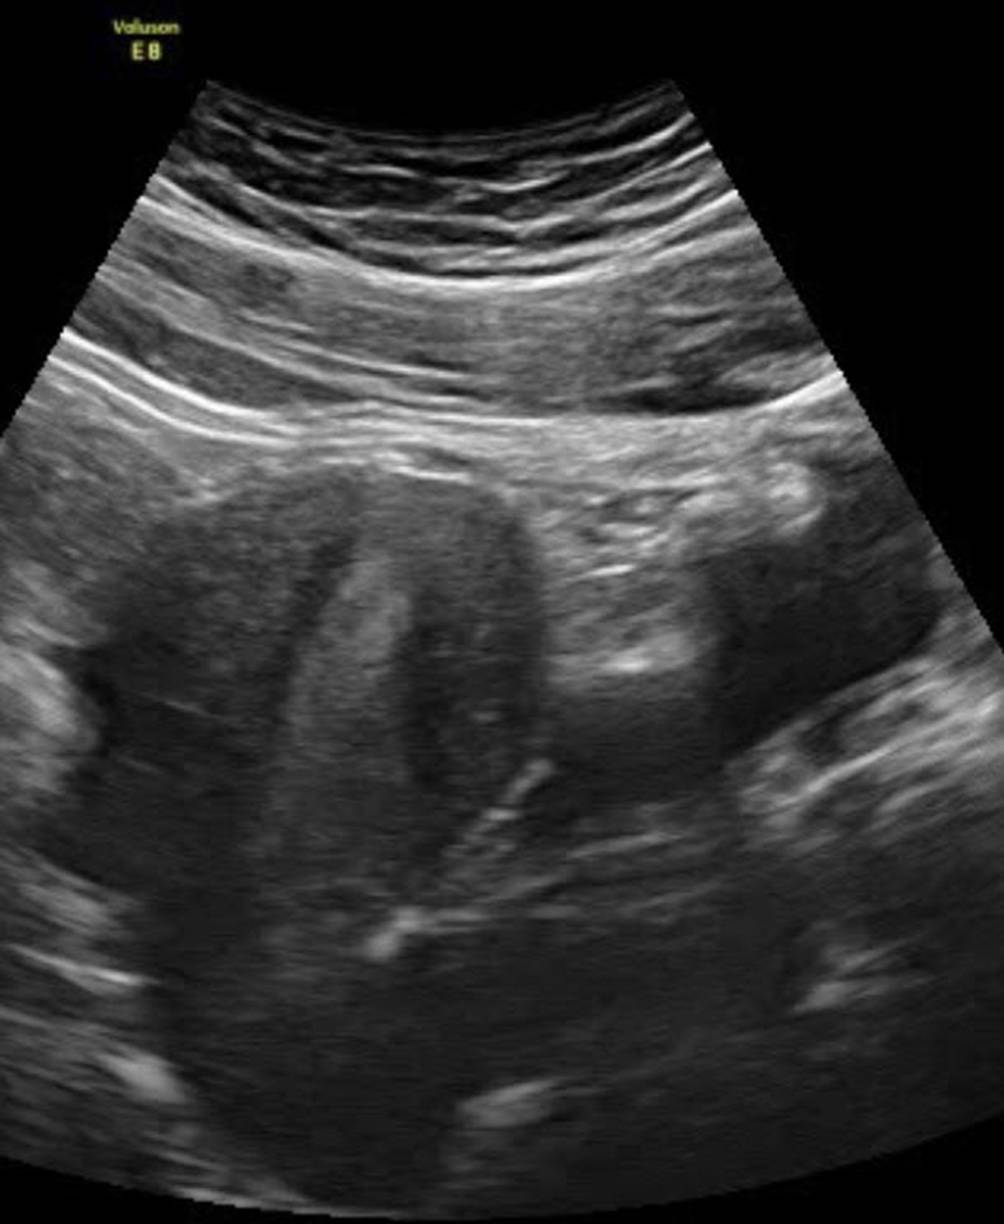

Abb. 15

Rechter Oberbauch mit Aszites bei OHSS. Die Messung der Flüssigkeit erfolgt auf Höhe des unteren Leberrands